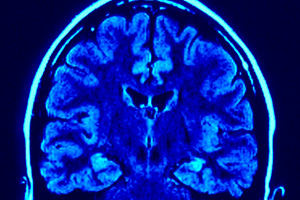

Диагностика. В целях постановки диагноза менингита проводится пункция с забором цереброспинальной жидкости на анализ из поясничного отдела позвоночника (люмбальная пункция). Дело в том, что при разных видах заболевания цереброспинальная жидкость выглядит по-разному: она может быть прозрачной или мутной, молочно-белой или кремовой, жёлтой или гнойной. Жидкость необходимо также изучить на предмет количества и состава клеток, качества белка, глюкозы, а также общих характеристик микрофлоры. Кроме этого, врачи прибегают к рентгенографии черепа, осмотру глазного дна, компьютерной и ядерно-магнитной резонансной томографии, электроэнцефалографии.